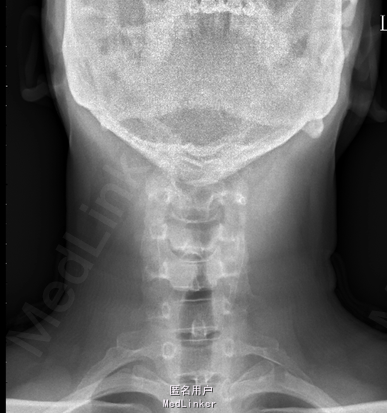

患者2年前无诱因出现后颈背部疼痛,呈胀痛性质,并伴有颈部及双上肢僵硬,休息后稍缓解,无头晕、恶心、呕吐等症状,就诊于其他医院,行MRI及颈部X片示:颅底凹陷症及寰枢椎脱位,建议患者手术治疗,患者要求暂行保守治疗,遂口服颈痛颗粒1包/tid、独一味胶囊3粒/tid、西乐葆200mg/bid,口服后症状未见明显缓解。6月前患者自觉颈背部疼痛发作频率增加,且疼痛时间延长及疼痛程度增加,同时伴右上肢麻木,并反复发作,为求手术治疗,患者来我院门诊,并以“颅底凹陷症 寰枢椎脱位”收入我科。

MRI及颈部X片示:颅底凹陷症及寰枢椎脱位

综上初步诊断:1、寰枢椎脱位;2、颅底凹陷症。